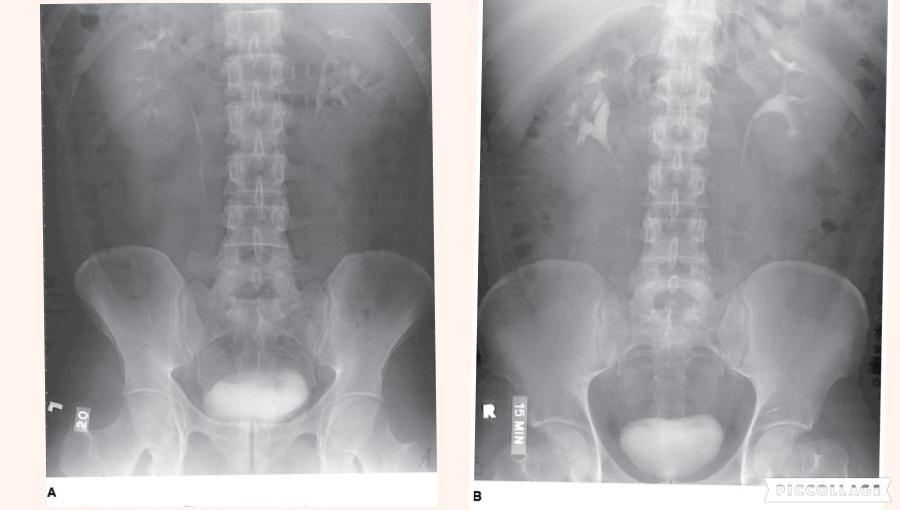

Which of the following statements referring to the images below is (are) correct?

- Image A was performed AP.

- Image B was performed AP.

- The AP image was obtained using ureteral compression.

2 only

The number 1 in the radiograph in Figure A represents which of the following renal structures?

Renal pelvis

In which of the following positions was the radiograph in Figure A taken?

LPO

The radiograph pictured in Figure A may be used to evaluate

1. polypoid lesions.

2. the lateral wall of the descending colon.

3. the posterior wall of the rectum.

1 and 2 only